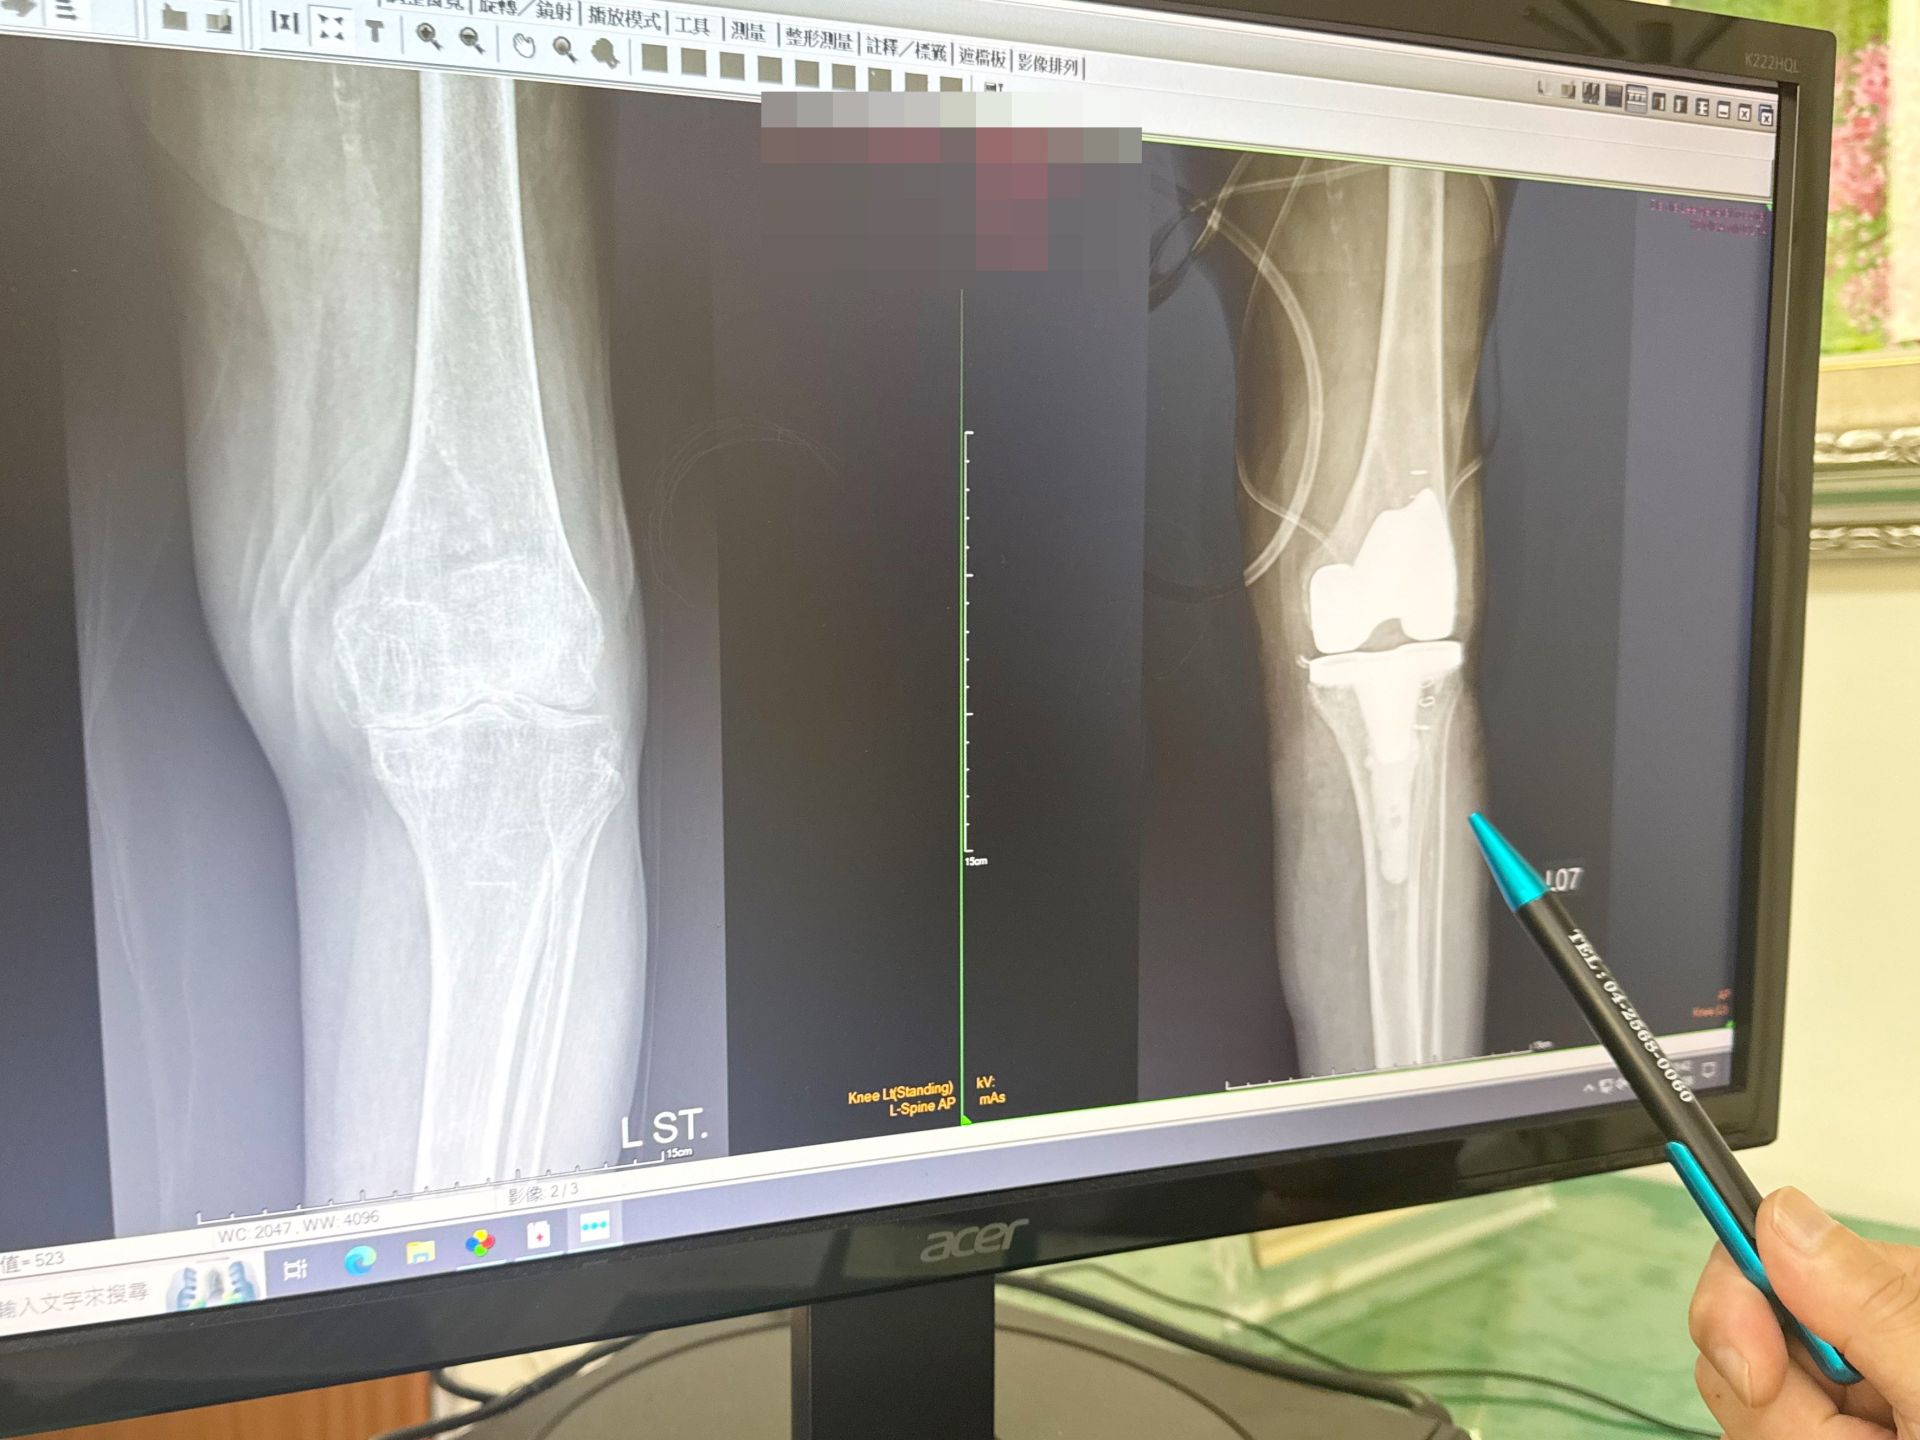

公用 一名百歲人瑞左膝關節退化,置換人工關節(右)

大甲李綜合醫院副院長、骨科主治醫師王芳英表示,阿嬤在兒子的陪同下前來門診,經過檢查後,確認阿嬤罹患第四期退化性關節炎,建議要手術替換人工關節才能改善生活的不方便,隔了一個禮拜,阿嬤自己決定開刀,兒子也同意讓母親手術置換人工膝關節。